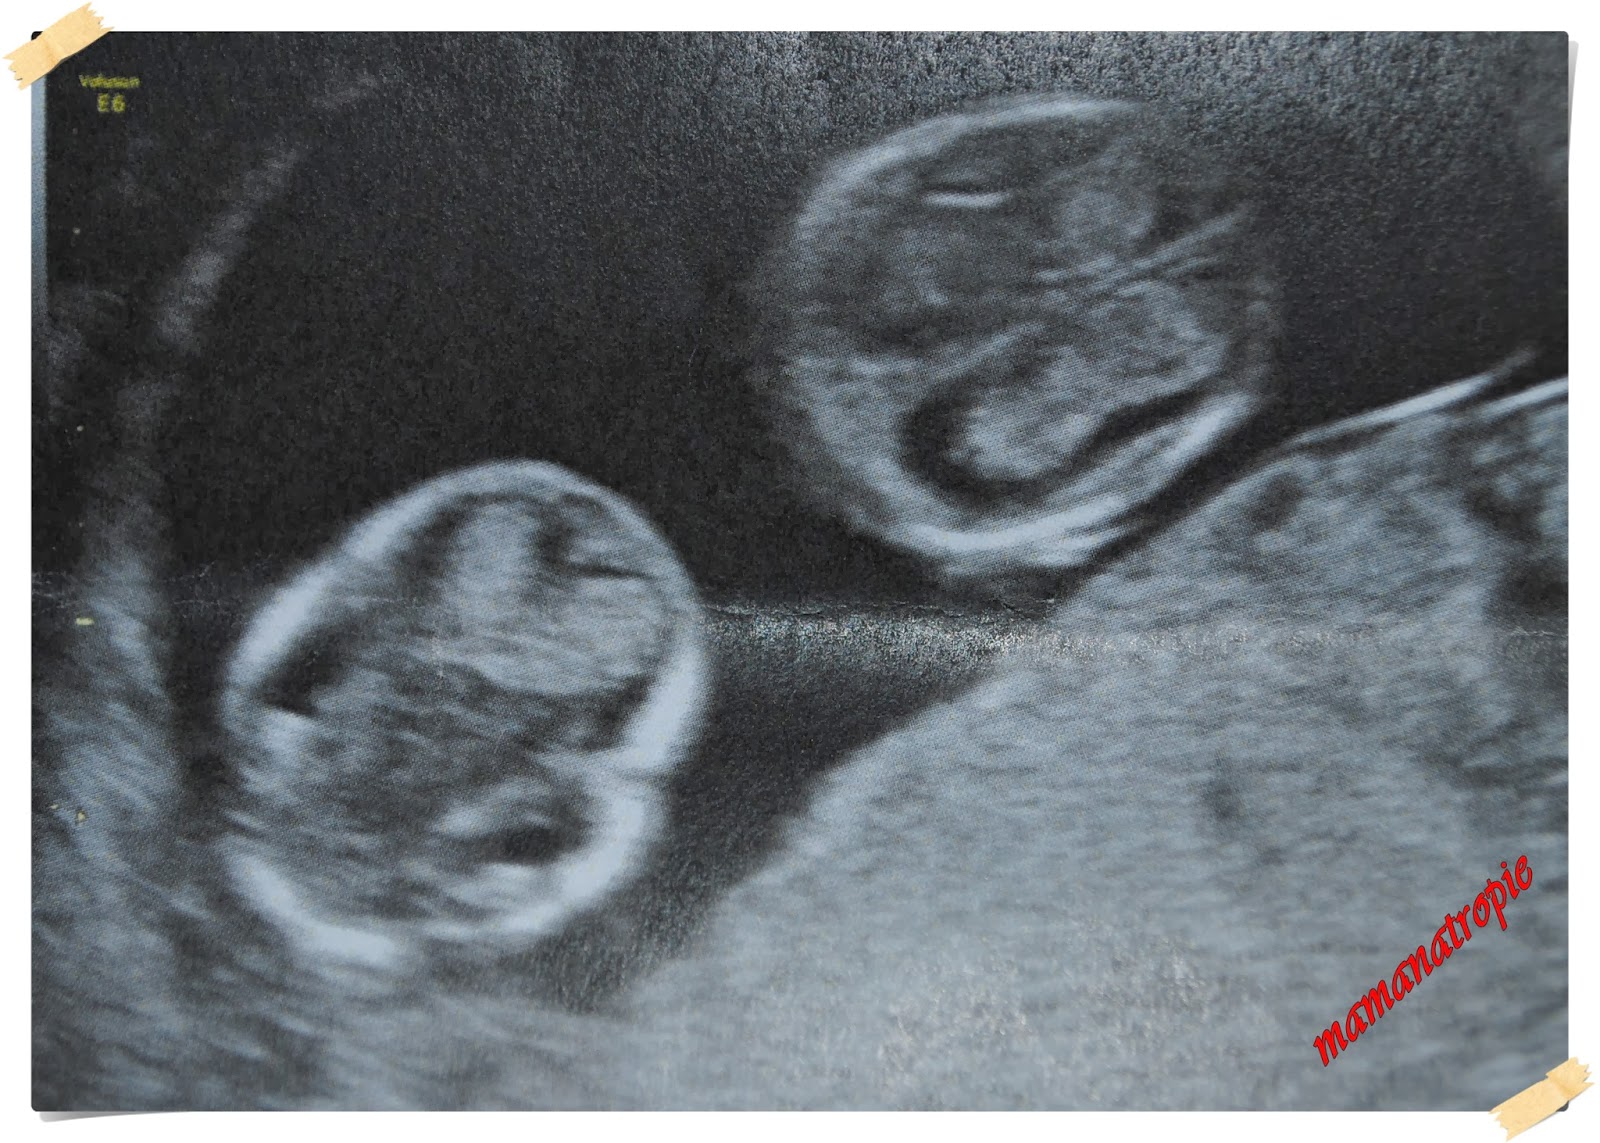

Ciąża biegnie swoim torem, tygodnie kolejne mijają. Ledwo niedawno pisałam Wam o moich pierwszych 10 tygodniach z bliźniakami <<TUTAJ>>, a już skończył się 16 tydzień. I nieubłaganie pędzi 17 tydzień bycia podwójną ciężarówką, już jest 17 tygodni i 3 dni. A zanim się obejrzę, pewnie już będę po połowie tej przygody z ciążą mnogą. Straszne:) No to zaczynamy..

14 tydzień. Niby szybko, minął niezauważalnie. Byliśmy 20.12 na usg, podpytałam o płeć. Nie żeby to było jakąś sprawą nadrzędną, ale człowieka zżera ciekawość. I rodzina i znajomi wciąż pytają. Mając już jednego małego chłopaka w domu, marzyłam o dziewczynkach. Niestety w tej chwili obraz usg sugeruje, że raczej będę matką 3 facetów. Czyli będzie istne szaleństwo:)

super wygladają dwa maluchy w brzuszku razem , rozczula mnie taki widok

Gratuluję bliźniaczków 😉 jak słodko to wygląda.

Ale urocze zdjęcia z USG 😉

Gratuluje:) cudownie wygladaja te zdjecia 🙂

o ja… fantastyczne zdjęcia maluszków 🙂

Gratulacje! 🙂 Pokaźne mieszkanko już mają Malutcy :))